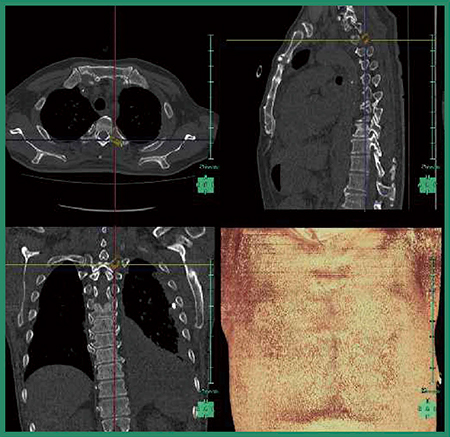

造影CTに経時差分を応用した骨転移候補の検出

経時差分は骨転移候補の検出に有用であるが,過去画像がなければ経時差分画像を作成できないという問題点がある。これに対する解決策の一つとして,単純CTと造影CTで差分を取ることを試みた。経時差分と言っても,必ずしも別の日のCT画像である必要はなく,同日の単純画像と造影画像の時間差でも,経時差分画像が作れるのではないかと考えた。

症例3は,肺がん術前の症例である。単純CTと造影CTで差分を取ると,T11に造骨性の骨転移があることが確認できた(図6 b→)。また,詳細に観察するとT7にもわずかに造影効果があり,差分画像で青く表示された(図6 a)。PET/CT検査では,差分画像でカラー表示された部位に一致してFDG集積が認められ(図6 c→),同日の単純画像と造影画像の差分検出に本ソフトウエアが活用できる可能性が示された。

図6 症例3:造影CTの差分画像による骨転移候補の検出